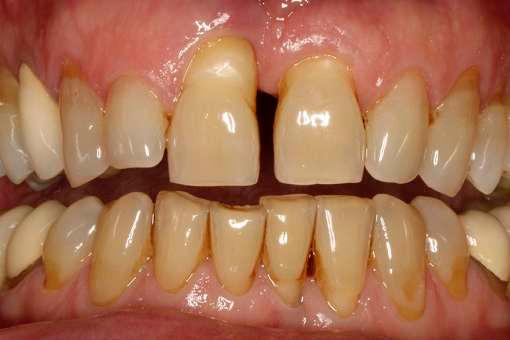

Negli ultimi anni sono presenti in letteratura studi che riportano riabilitazioni implantoprotesiche effettuate in questa tipologia di pazienti , fornendo loro nuove prospettive terapeutiche.

Con una pianificazione attenta, una collaborazione multidisciplinare e l’applicazione di linee guida aggiornate, anche le persone con MEC, possono ricevere le cure odontoiatriche necessarie, mantenendo la salute orale e potendo esibire con serenità un bel sorriso!